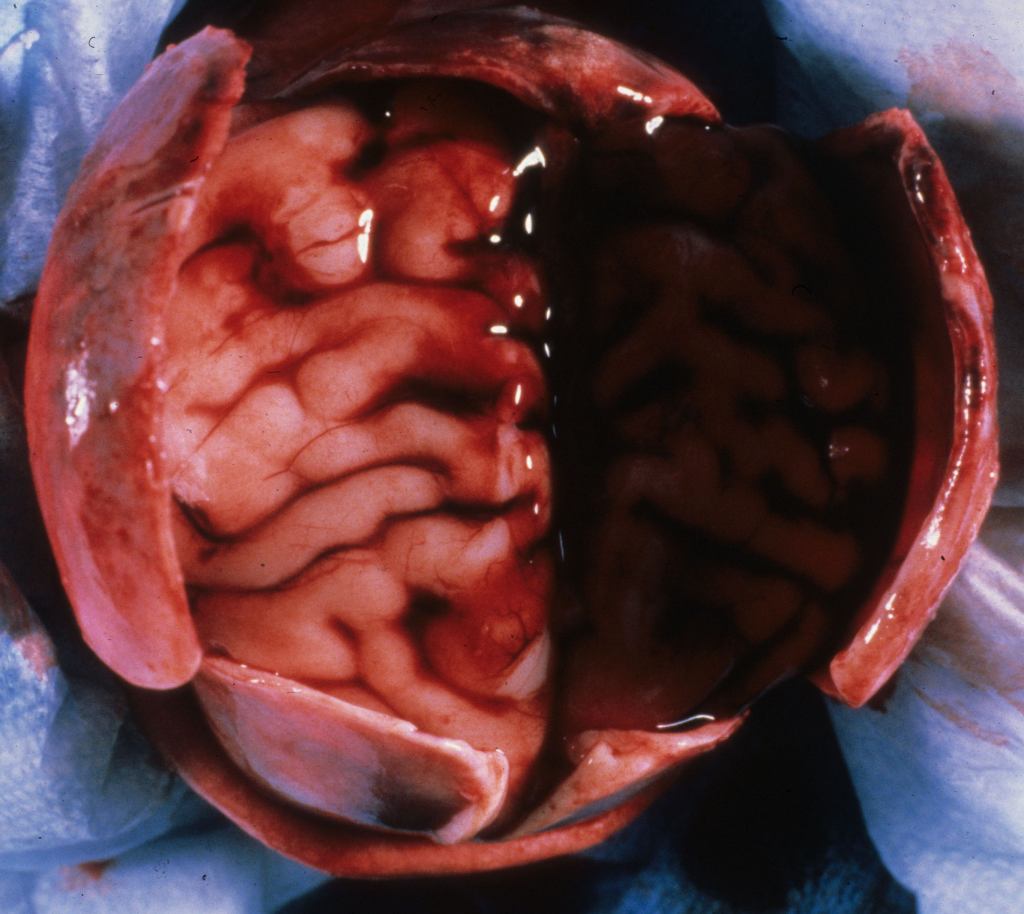

Intraventricular hemorrhage (IVH):

Intraventricular hemorrhage is usually the result of germinal matrix hemorrhage or hemorrhage from periventricular leukomalacia. The germinal matrix exists from early gestation to term as a reserve of immature cells that will become neurons and glia. The amount decreases after 33 weeks of gestation. The risk of IVH synchronously decreases with the maturation of the germinal matrix. Hemorrhage in this soft embryonic appearing tissue with prominent thin-walled vessels may occur in response to various risks including hypoxia, cytokines, or suddenly changing vascular pressures. Most hemorrhages are identified after birth. However, intraventricular hemorrhage can be found in previable fetuses at autopsy (Fig 1).

Grossly, in the intact brain, blood in the ventricles often seeps and pools around the base of the brain (Fig 2).